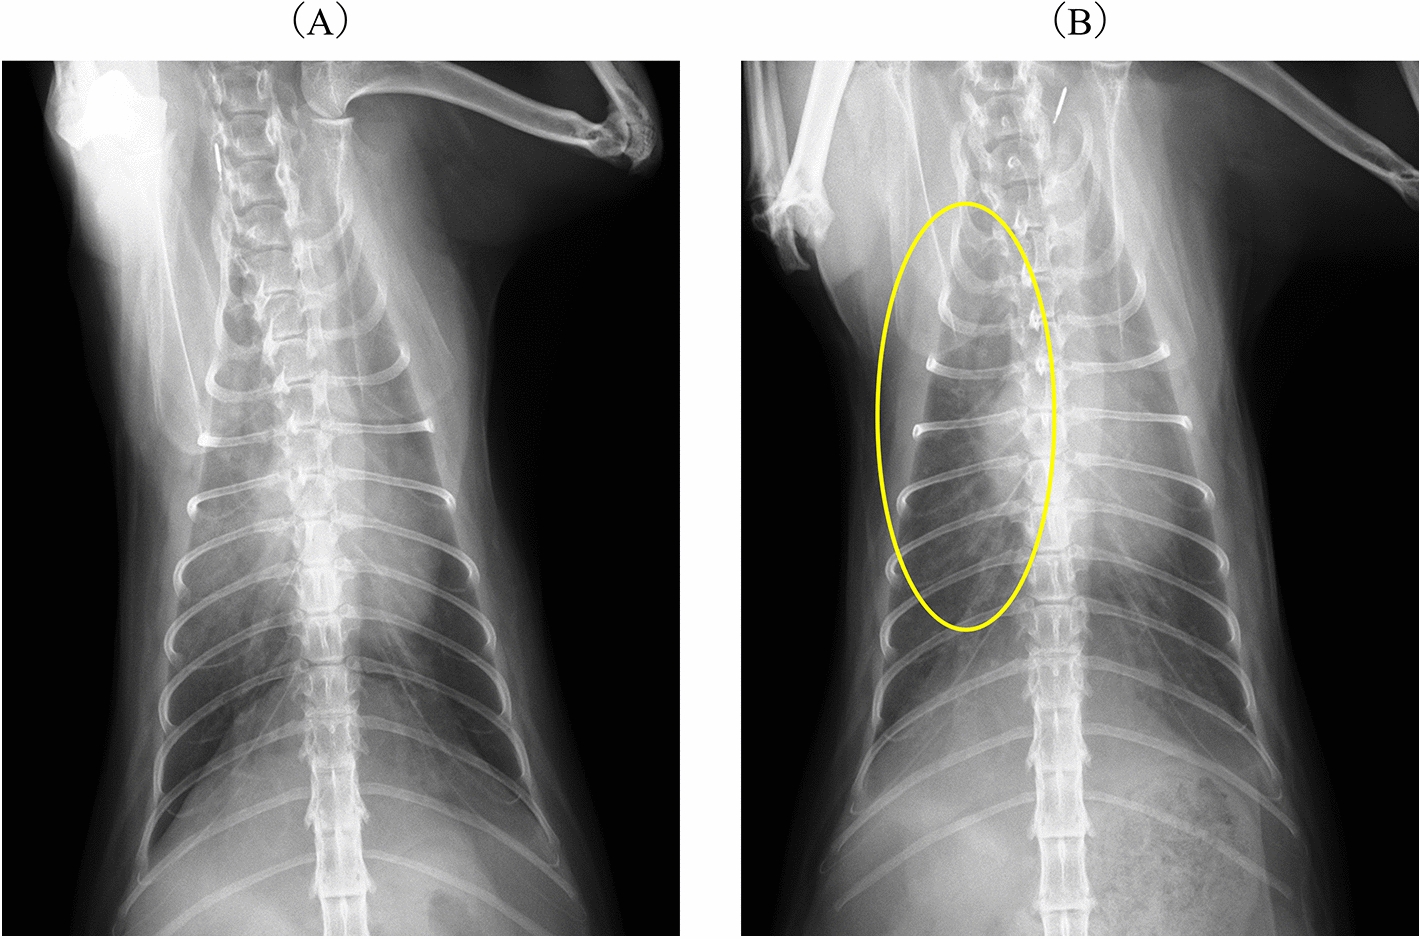

Case presentation: A 2 year-old Norwegian Forest cat was diagnosed with pulmonary oedema and PH secondary to cor triatriatum sinister (CTS) and showed improved breathing following two subcutaneous furosemide treatments, 1 and 2 mg/kg, during an overnight stay at the referral veterinary hospital. Sildenafil alone (0.69 mg/kg, PO, BID) was prescribed post-discharge to address PH without diuretics. Post-discharge from the referral veterinary hospital, collapse and pre-syncope were suspected to be due to PH. Consequently, sildenafil was titrated weekly, starting at 1.09 mg/kg BID and increasing to 1.63 mg/kg BID. Pre-syncope and collapse resolved, and pulmonary opacities reduced considerably, although concerns remained that increased pulmonary blood flow to suspected CTS from sildenafil might worsen cardiogenic pulmonary oedema. The patient was also treated with rivaroxaban (2.5 mg/head, SID), considering the increased risk of thrombus formation due to blood flow stasis and endothelial damage. Thirty-eight days later, the cat presented for the first time to our hosipital (Azabu University Veterinary Teaching Hospital) for examination. On echocardiography, a continuous mosaic blood flow (maximum and minimum velocity, 3.14 m/s; estimated pressure gradient, 39.4 mmHg) was observed in two enlarged pulmonary veins. Pulmonary artery enlargement (main pulmonary artery to thoracic aorta ratio: 1.90), pulmonary vein stenosis (PVS), and diffuse bilateral ground-glass lung opacities were observed using computed tomography. PH with unilateral PVS involving two out of the three right pulmonary veins, specifically the right cranial and right middle pulmonary veins, along with pulmonary parenchymal disease, was diagnosed. The cat was further treated with furosemide (1 mg/kg, BID, PO) with no clinical signs but succumbed to acute dyspnoea 51 days after the first visit.

背景:猫的肺动脉高压(PH)检测可能具有挑战性。肺静脉狭窄(PVS)在猫中很少见,可导致ph。唯一报道的PVS病例接受了尸检诊断。在猫的一生中成像确定了本病例的诊断。病例介绍:一只2岁的挪威森林猫被诊断为肺水肿和PH继发于心房三房性心脏病(CTS),在转诊兽医医院过夜期间,两次皮下速尿治疗(1和2 mg/kg)后呼吸改善。出院后单独开西地那非(0.69 mg/kg, PO, BID)处理PH,不使用利尿剂。从转诊兽医院出院后,怀疑是ph引起的晕倒和晕厥前期。因此,每周滴定西地那非,从1.09 mg/kg BID开始,增加到1.63 mg/kg BID。晕厥前期和虚脱消退,肺混浊明显减少,尽管仍然担心西地那非导致疑似CTS的肺血流量增加可能加重心源性肺水肿。考虑到血流停滞和内皮损伤导致血栓形成的风险增加,患者还接受了利伐沙班治疗(2.5 mg/头,SID)。38天后,猫首次到我院(麻布大学兽医教学医院)检查。超声心动图显示连续的马赛克血流(最大和最小速度为3.14 m/s;估计压力梯度,39.4 mmHg)。ct示肺动脉扩张(主肺动脉与胸主动脉比值:1.90),肺静脉狭窄(PVS),双侧弥漫性磨玻璃肺影。诊断为PH伴单侧PVS累及右肺三条静脉中的两条,特别是右颅静脉和右中肺静脉,同时伴有肺实质疾病。猫进一步给予速尿(1 mg/kg, BID, PO)治疗,无临床症状,但在第一次就诊后51天出现急性呼吸困难。结论:局部肺泡型且无左房扩大的幼猫应考虑单侧PVS,因为预后可能较差。严重PH伴PVS可与肺部疾病共存。如果使用西地那非,应以低剂量开始并密切监测。